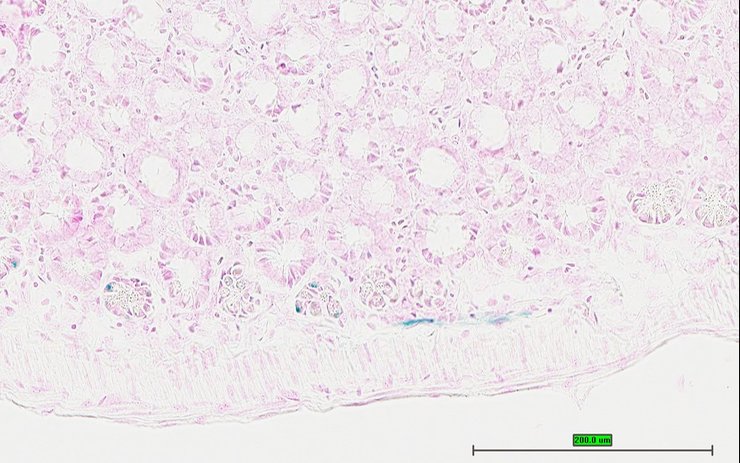

TS28: ileum Present UC Davis_1875947

TS28: ileum Present UC Davis_1875963

Specimen UC Davis_1875964: postnatal adult; Ppbptm1.1(KOMP)Vlcg/Ppbp+ (more )

Structure Level Pattern Image Note

TS28: ileum Present UC Davis_1875964